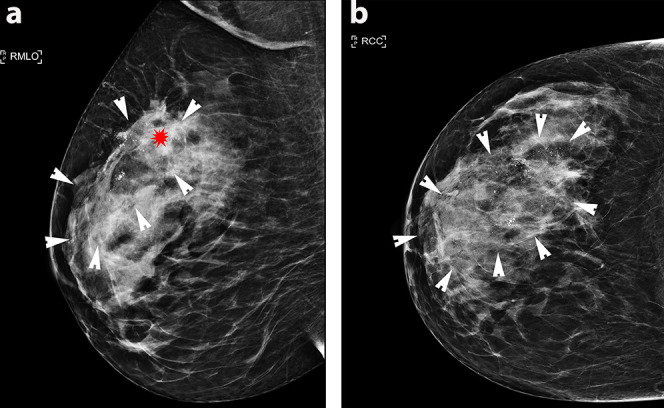

超极化 13C 磁共振成像(HP-MRI)是一种新型成像技术,可对体内代谢途径进行实时分析1 。随着分子生物学知识的发展,人们越来越清楚地认识到癌细胞代谢与疾病结果的关系,其中乳酸引起了特别关注。2 近期对乳腺癌筛查项目的审查引起了人们的关注,并提高了公众对过度治疗的认识。科学界需要将重点从单纯提高癌症检测率转移到寻求新的方法来区分侵袭性乳腺癌和仍将保持不扩散的乳腺癌。HP-MRI 为识别侵袭性肿瘤表型和帮助监测/预测治疗反应提供了机会。在此,我们报告了首例使用 HP-MRI 和包括乳腺 MRI 在内的相关传统成像技术进行成像的乳腺癌病例。

Hyperpolarised 13C MRI (HP-MRI) is a novel imaging technique that allows real-time analysis of metabolic pathways in vivo.1 The technology to conduct HP-MRI in humans has recently become available and is starting to be clinically applied. As knowledge of molecular biology advances, it is increasingly apparent that cancer cell metabolism is related to disease outcomes, with lactate attracting specific attention. 2 Recent reviews of breast cancer screening programs have raised concerns and increased public awareness of over treatment. The scientific community needs to shift focus from improving cancer detection alone to pursuing novel methods of distinguishing aggressive breast cancers from those which will remain indolent. HP-MRI offers the opportunity to identify aggressive tumour phenotypes and help monitor/predict therapeutic response. Here we report one of the first cases of breast cancer imaged using HP-MRI alongside correlative conventional imaging, including breast MRI.